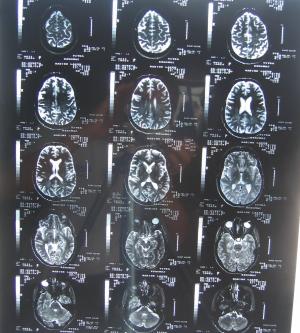

Life continues to be beautiful at the Casas Laxen. The

best news of the season is that Nadine is healthy once

again, and overcame a brain tumor that was diagnosed

early this year. She went in for a routine blood test,

and the results came back that her prolactin levels were

over 200. Normal is under 20. This meant she probably

had a growth in her pituitary gland, which was confirmed

with an MRI (shown at left) a few days later. Her

neurologist, Dr. Santana, put on on bromocriptine, a

very nasty drug that attacks the pituitary tumor. We got

the good news in July, that the tumor had disappeared,

and we have been celebrating ever since.